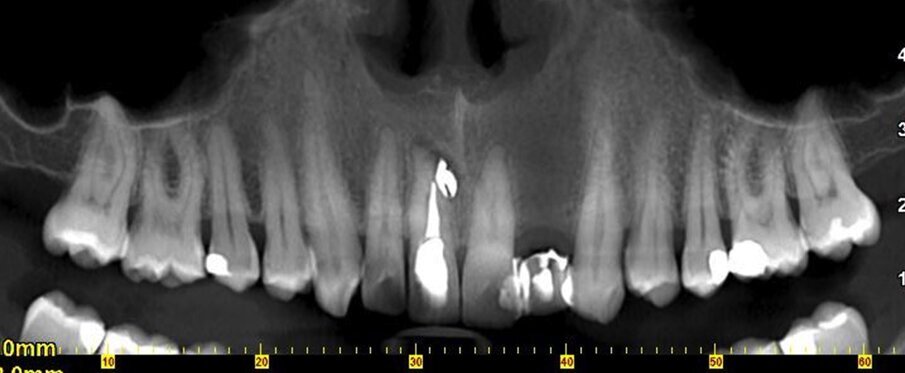

Nel maggio 2015 un insegnante quarantenne si rivolge ad un odontoiatra per estrarre e sostituire con un impianto l’incisivo laterale superiore di sinistra, 22. In tale occasione scopre la necessità di trattare endodonticamente l’incisivo centrale destro, 11 (l’odontoiatra non ha documentazione a riguardo), trattamento che, nonostante risulti lungo e complesso, viene terminato nel settembre dello stesso anno con piena soddisfazione dell’odontoiatra.

Nei primi mesi del 2016, tuttavia, il paziente perde l’impianto in sede 22, ha fastidio nel settore frontale e nota un “brufolino”, ma per il professionista è tutto a posto. Non convinto, l’insegnante effettua una consulenza da un altro odontoiatra e scopre che il dente 11 ha dei problemi. È compromesso da un processo infettivo cronico (area di rarefazione radiograficamente evidenziabile) con evidenza radiografica e una fistola, prima inesistente. C’è una perforazione iatrogena della radice del dente, con sbuffo di materiale radiopaco nel parodonto.

In parole semplici il paziente scopre che la terapia è stata mal eseguita e ha prodotto un danno (falsa strada). Risulta necessario un secondo intervento ortogrado e retrogrado da parte di uno specialista in endodonzia dal costo di 850 euro. Ai controlli successivi le problematiche rientrano. Il giovane insegnante protesta con il primo odontoiatra, chiede indietro quanto ha speso per il trattamento del dente 11 (ossia 250 euro) e per l’intervento endodontico di recupero del dente, 850 euro, per un totale di 1.100 euro.